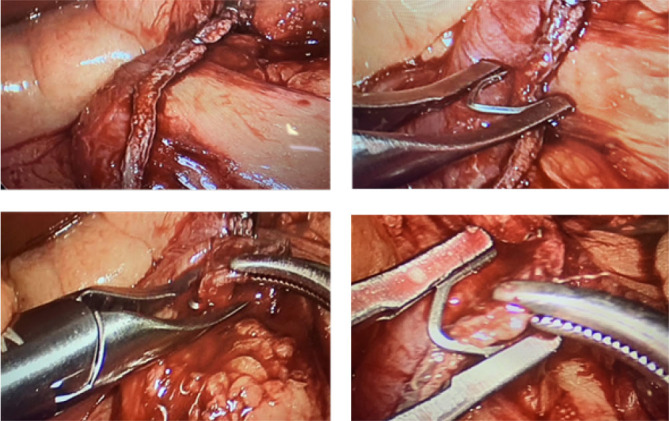

Methods: Ninety-eight patients were submitted to gastric surgery, divided into three groups: laparoscopic sleeve gastrectomy (LSG) (n=47), Roux-en-Y gastric bypass (LRYGB) (n=30), and laparoscopic distal gastrectomy (LDG) (n=21). Motorized staplers were employed in 61 patients. The number of firings, number of clips, time of total firings, total time to complete the surgery, and postoperative outcome were recorded in a specific protocol.

Results: Patients submitted to LSG, LRYGB, and LDG recorded a shorter time to complete the procedure and a smaller number of firings were observed using motorized stapler (p<0.0001). No differences were identified regarding the number of clips used in patients submitted to LSG. In the group that used mechanic stapler to complete gastrojejunostomy, jejuno-jejuno-anastomosis, and jejunal transection, it was observed more prolonged time of firing and total time for finishing the procedure (p=0.0001). No intraoperative complications were found comparing the two devices used. Very similar findings were noted in the group of patients undergoing LDG.